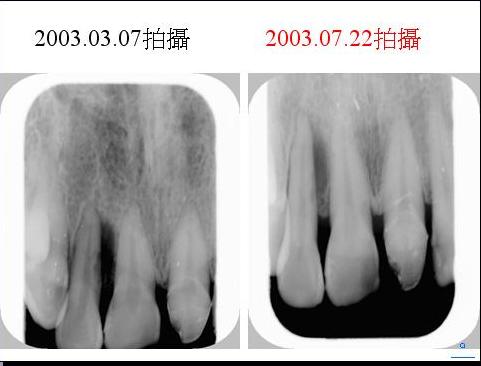

一.牙周病經雷射治療後牙周(齒槽骨)的修復